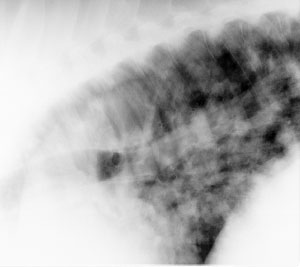

Quarter horse with external abscess, fever, and cough

A radiograph (lateral view) of the caudal thorax is shown. Which of the following is a correct description of the radiologic findings?